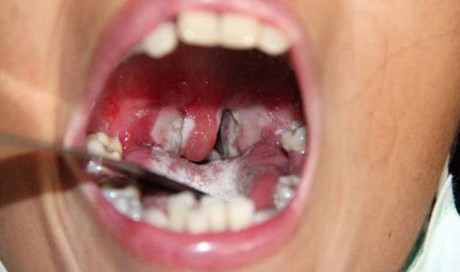

Bệnh bạch hầu là một căn bệnh truyền nhiễm do vi khuẩn Corynebacterium diphtheriae gây ra. Vi khuẩn này tạo ra độc tố gây tổn thương da và niêm mạc tại chỗ, hoặc độc tố vào máu gây ra các tổn thương ở cơ quan khác như hệ thần kinh, tim mạch, thận. Tại khu vực tổn thương xuất hiện một lớp màng màu trắng ngà bao phủ, phát triển và tích tụ trong mũi và cổ họng, có thể dẫn đến ngạt thở.

Lớp màng trắng trong cổ họng người bệnh bạch hầu - Ảnh minh họa

- Xuất hiện một màng dày trắng ngà bao phủ cổ họng, amidan, thanh quản, mũi, lưỡi… Đây cũng chính là dấu hiệu điển hình của bệnh bạch hầu.

- Lớp màng trắng trong cổ họng người bệnh bạch hầu